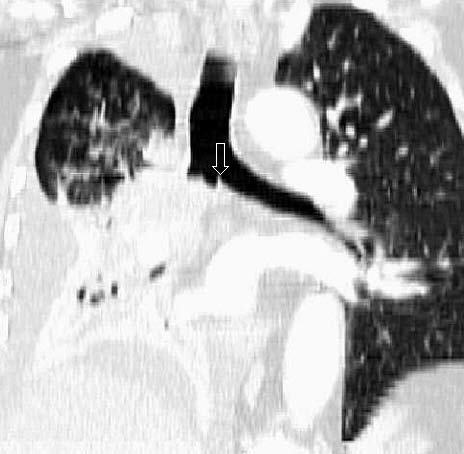

Fig. 13.--Metástasis pulmonares. (A) Atelectasia del lóbulo inferior izquierdo secundaria a tumor central con nódulo pulmonar contralateral (flecha). (B) Proyección de máxima intensidad (MIP) de 15 mm al mismo nivel que muestra más nódulos (flechas).